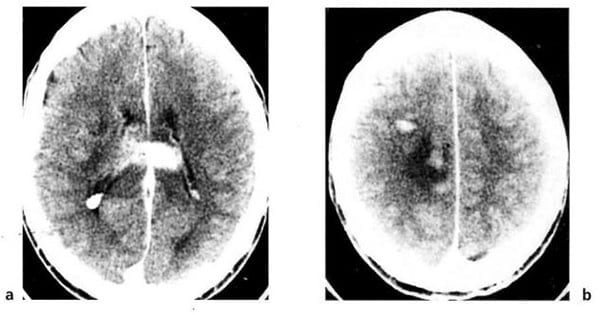

Hình 1.46. Khối máu tụ dưới màng cứng hỗn hợp cấp và mãn trong khối tụ bên trái. Mật độ cao trong khối lớn mật độ thấp tương ứng máu tươi bên trong một khối tụ máu mật độ thấp mãn tính.

Hình 1.47. Khối máu tụ bán cấp dưới màng cứng có mật độ ngang. Trước tiêm, chỉ thấy hiệu ứng choán chỗ và xóa mất não thất bên bên trái (a). Sau tiêm (b), các tĩnh mạch bề mặt hiện lên (mũi tên) cho thấy rõ hơn ranh giới của khối tụ máu.